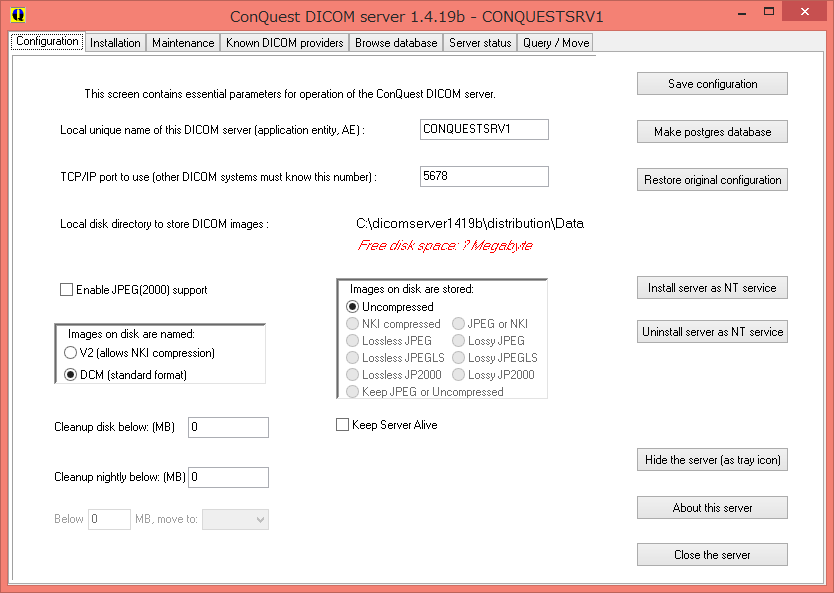

PACS接続に必要なAEタイトルを設定します。

AEタイトルは、医療機器、ビューアも含めてすべて固有ものもでなければなりません。

ネットワーク内で名前が重複しないように気をつけましょう。

デフォルトでは「CONQUESTSRV1」になっています。

今回は、デフォルトのまま「CONQUESTSRV1」で設定します。

ここでは、ポート番号を設定します。

ポート番号は、そのPC上で固有のものでなければなりません。

今回は、デフォルトのまま「5678」で設定します。

ここでは、転送したDICOM画像の格納場所を選択できます。

デフォルトでは、CONQUESTの展開フォルダ([ConquestDICOMServer.exe]があるところ)の中にある[Data]フォルダにDICOM画像が格納されるようになっています。

ここでは、DICOM画像の圧縮形式等を設定できます。

今回は圧縮しないという「Uncompressed」を選択します。

また、「Keep Server Alive」にチェックを入れておくと、常にサーバプロセスが起動した状態になります。

圧縮画像を取り扱う場合は、「Enable JPEF(2000)suppoert」にチェックを入れて圧縮形式を選択して下さい。

最後に、右上にあるこの「Save configuration」を押して、設定を保存して下さい。

すると、自動で「Installation」のタブに移動します。